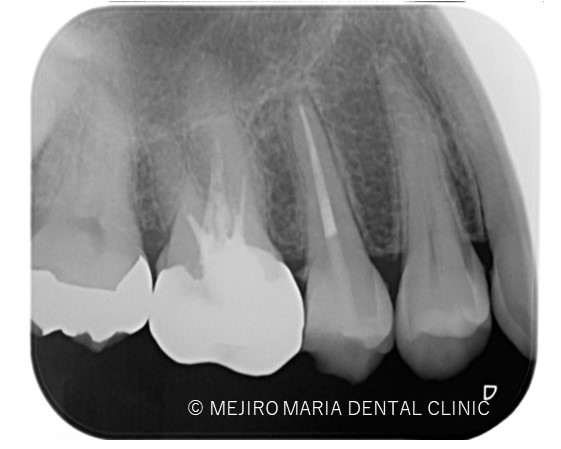

治療後の様子

*赤丸で示しているところは、根が分岐している箇所を示す

3ヶ月後に経過観察を行い。最終的な根管治療の予後を確認する予定です。 可及的速やかに暫間冠の作製、問題なければ最終補綴処置に移行します。